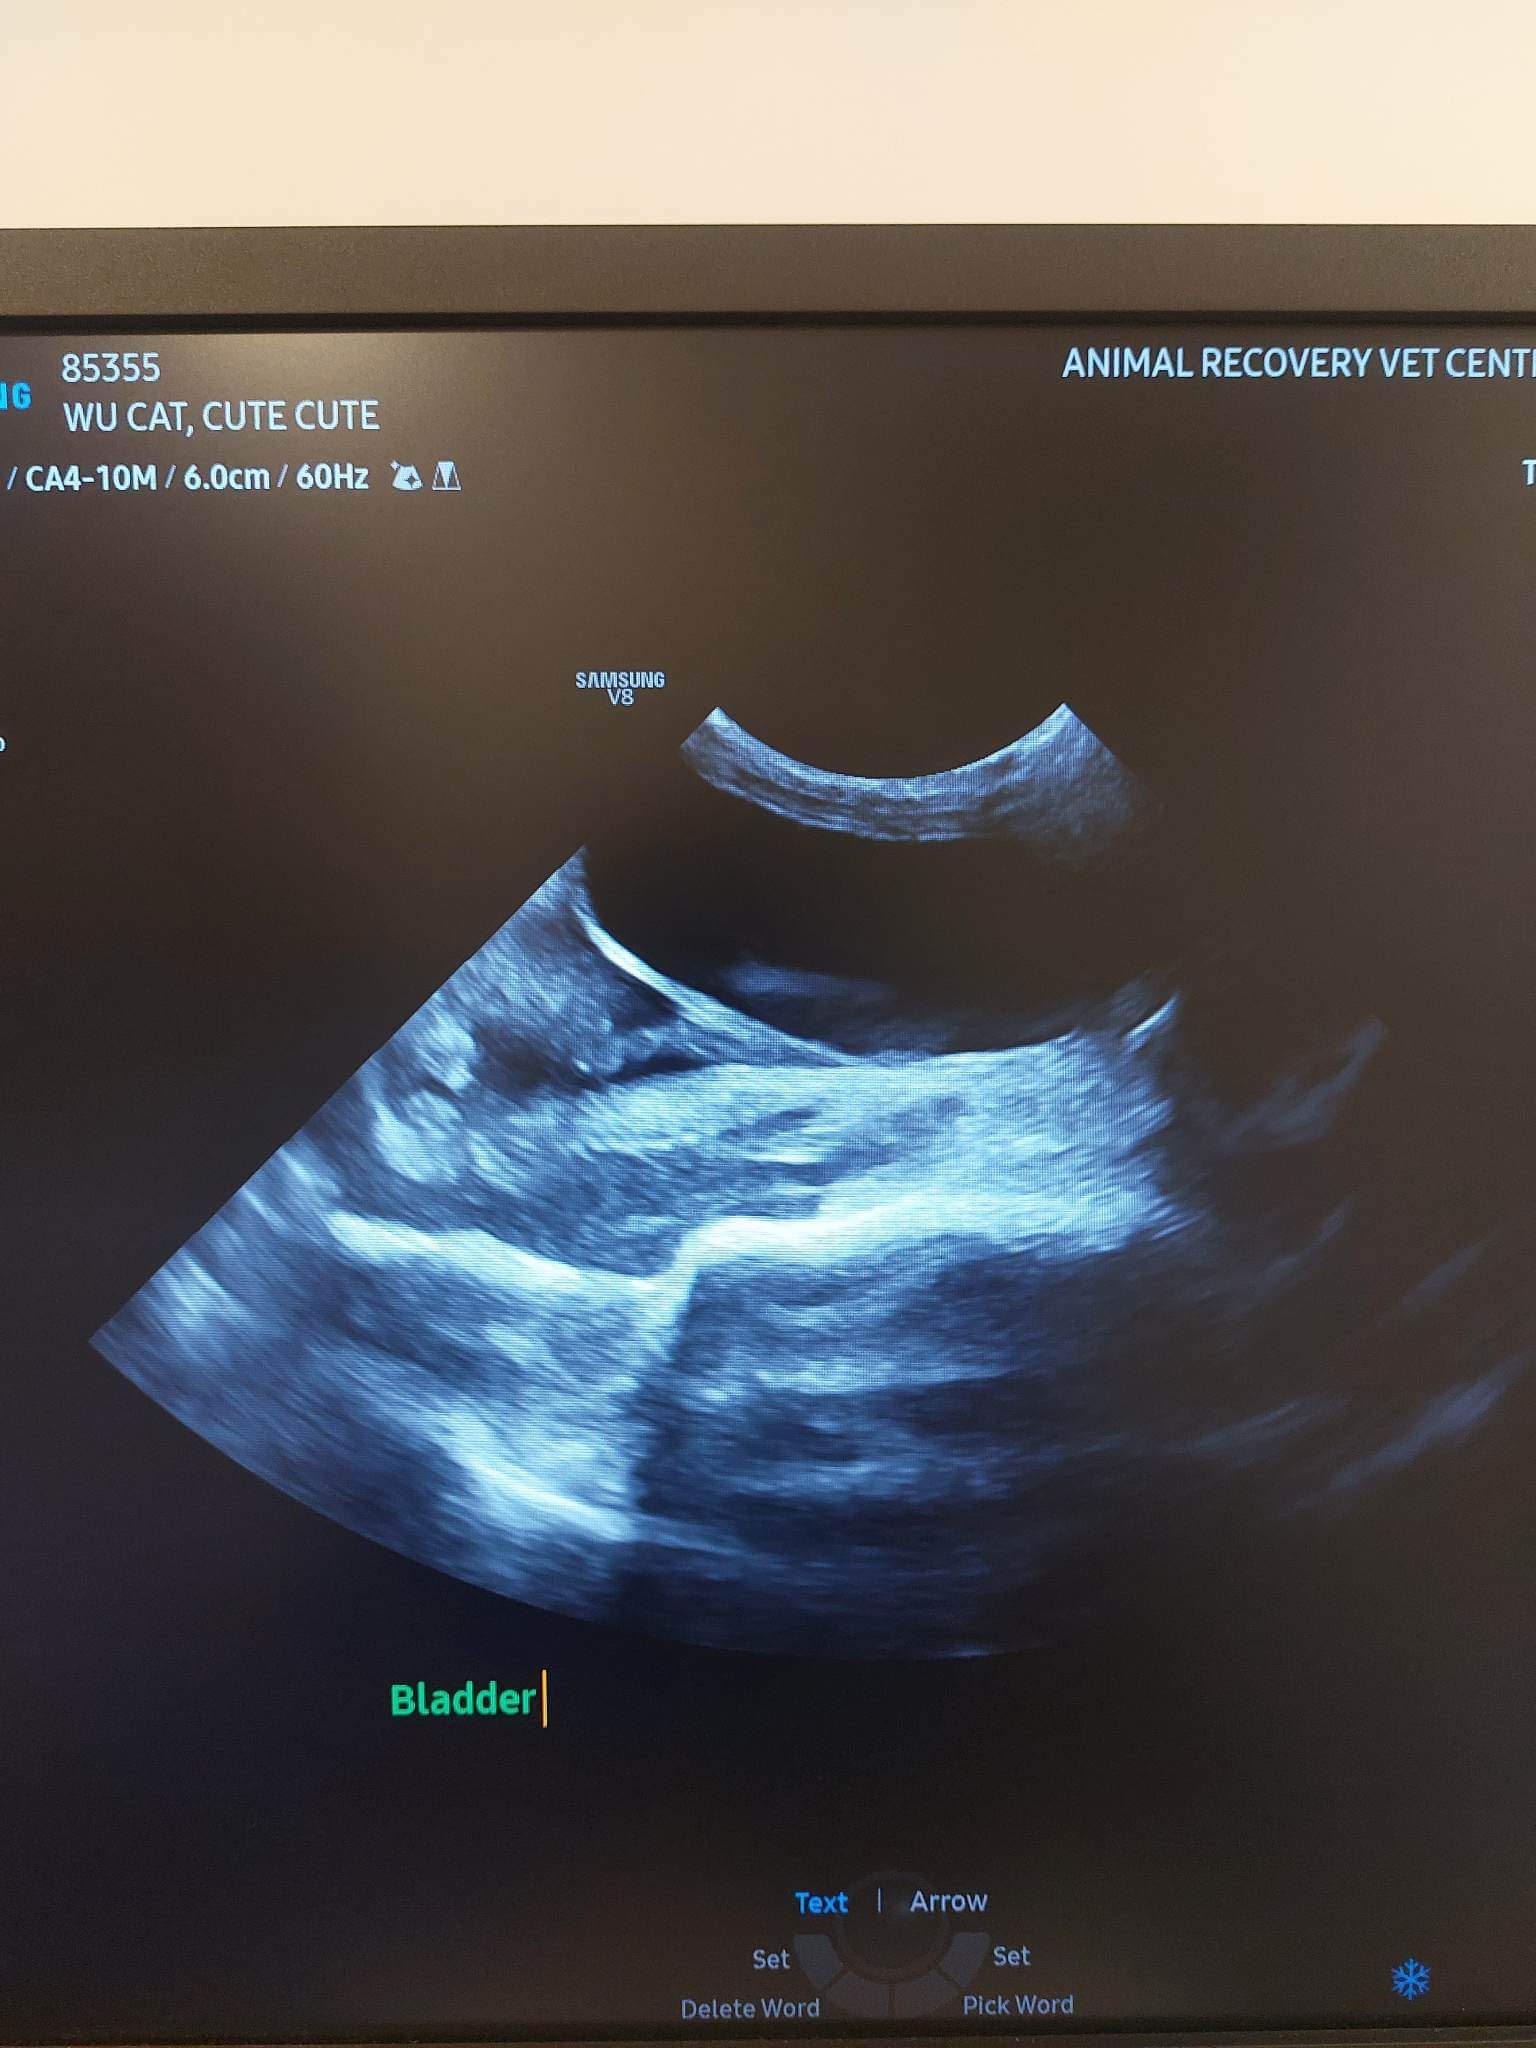

1040am: Dr yeumee bring cute in to shave a bit and get ready for u/s

U/s: core findings: highly is lymphoma. Super enlarged spleen (only good news is no sign of showing bleeding fr spleen yet), enlarged liver. Multiple masses in abdomen, all highly point to cancer (I’ll start pred 0.5mg/kg per feed, ie 1.25mg x twice a day) – pred will help in boosting rbc also. Intestine thickening also.

Fluid in chest and lungs- not drawing out not a lot yet.